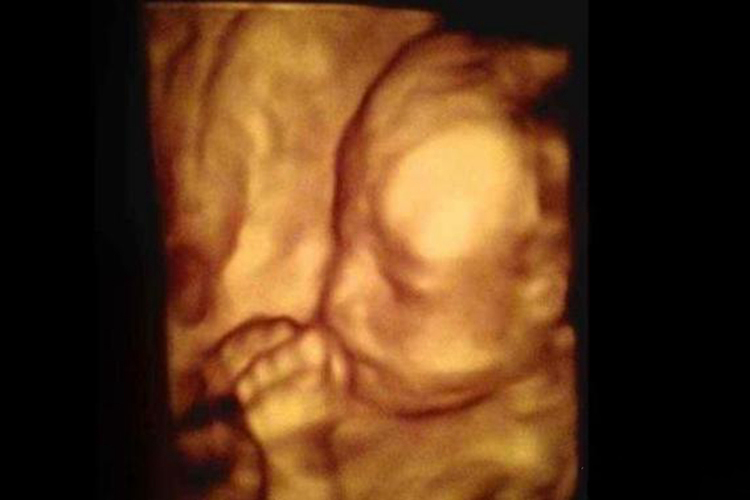

怀孕19周时已经能够从外生殖器确认胎儿性别,胎儿头皮已经长出毛发,皮肤菲薄,颜色在深红和暗红之间,可能会出现少量的皮下脂肪,部分孕妇可能会自觉胎动。此时胎儿的呼吸系统、消化系统、泌尿系统已经建立,能够吞咽羊水、开始出现呼吸运动、膀胱内已经有尿液。